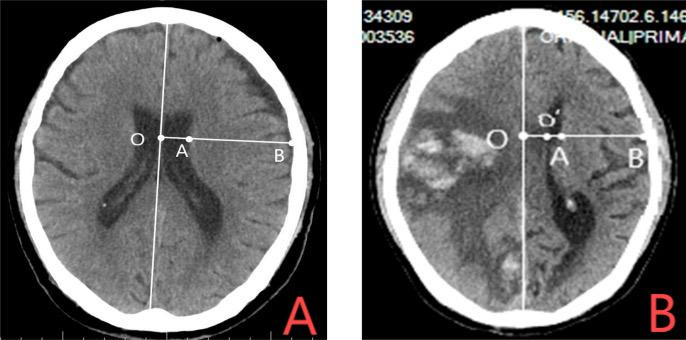

穿刺前侧脑室大小分级评估:本研究采用改良单尾指数(modified unilateral caudate index,MUCI)评价LHI狭小侧脑室的大小[15]。双尾指数(caudate index,CI)是反映急性脑积水脑室扩大的常用指标,但对于神经急重症侧脑室移位、变形、狭小时,在反映穿刺侧脑室前角的难易度时仍欠缺,因此本研究者曾参照双尾指数测量原理及有关文献[20-21],制定出在神经急重症合并侧脑室狭小和中线移位时的侧脑室大小级别的判断标准,即改良单尾指数[15](见图 2),方法如下:在测量CI指数平面(尾状核头上部所在平面,约在OM线上5~6 cm),穿刺侧的侧脑室前角宽度/同部位颅脑半径=OA/OB(中线结构不移位)(图 2A)或=O’A/OB (中线结构移位)(图 2B),判定正常或狭小脑室 < 0.12(45岁以下),0.14(46~55岁),0.16(56~65岁),0.17(> 65);本组病例超过以上界限者定义为脑室扩大。其中扩大的侧脑室分级标准参照Evans指数标准,轻度扩张为Evans指数0.3~0.4[22]。

|

| 注:大面积脑梗死改良单尾指数测定:A图示中线结构不移位时,穿刺侧的侧脑室宽度/同部位颅脑半径=OA/OB;B图示中线结构移位时,穿刺侧的侧脑室宽度/同部位颅脑半径=O'A/OB 图 2 改良单尾指数对穿刺侧的侧脑室大小级别判定 Fig 2 Determine the size category of the lateral ventricle on the puncture side through MUCI |